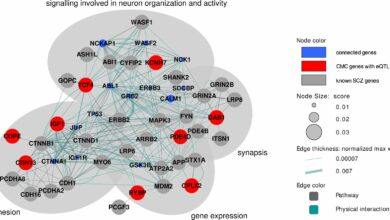

A análise de big data fortalece a luta contra a doença de Alzheimer

Um técnico do PNNL estuda uma amostra de tecido cerebral. Crédito: Andrea Starr / Pacific Northwest National Laboratory A doença…